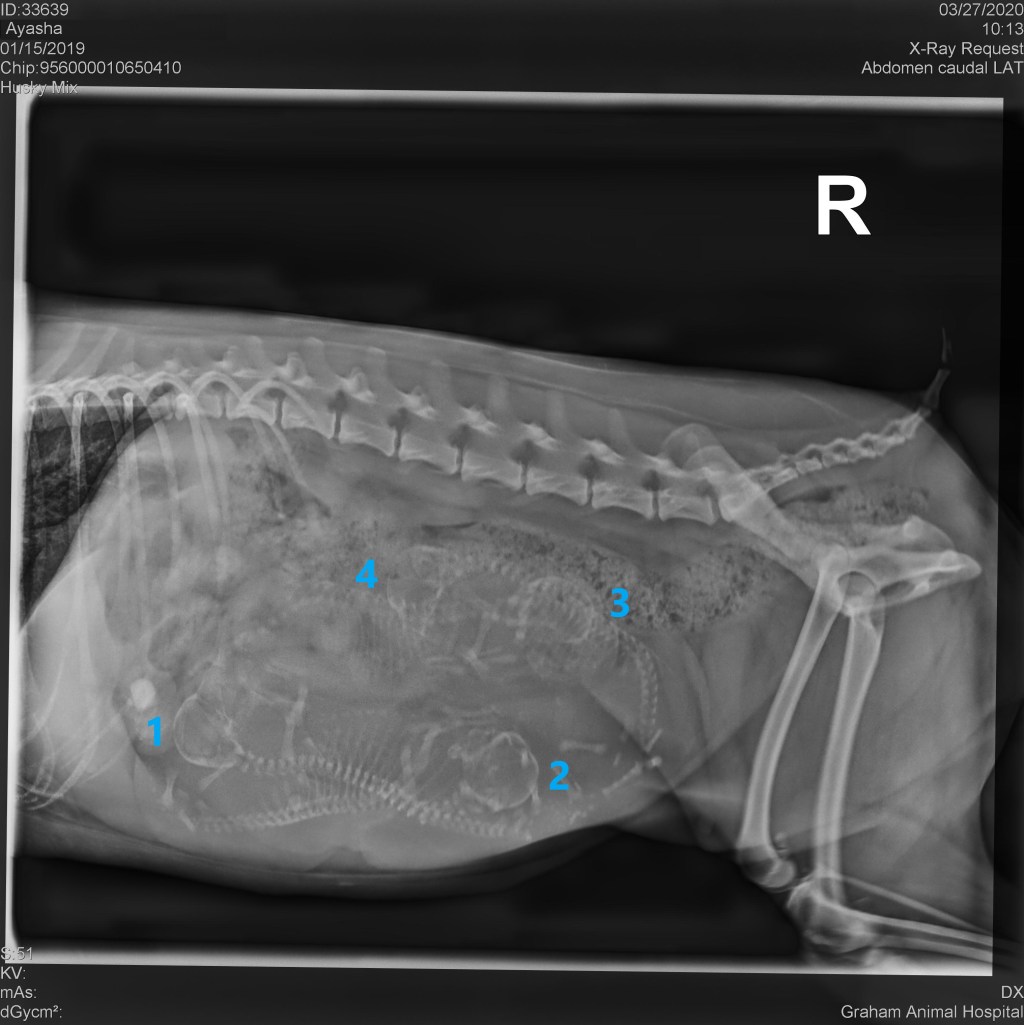

Ayasha had her pre-partum puppy count x-ray today, and the vet confirmed that we are expecting 4 precious puppies! Ayasha is due as early as as tomorrow (March 28), but most likely will have her pups in 5 days or so. We can’t wait to meet these little fluffies!